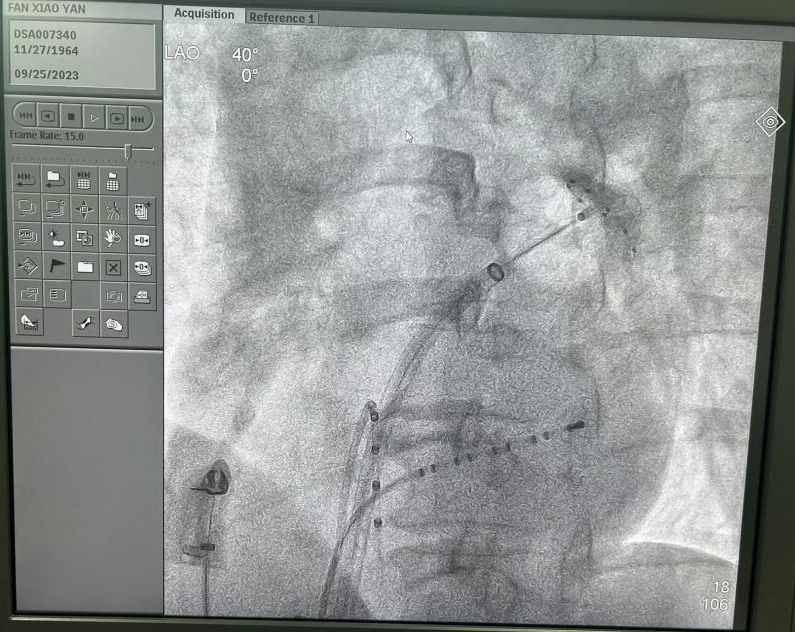

心血管内科副主任陈弹带领电生理团队对范阿姨的左心房三维重建图像进行仔细分析,并在多次病例讨论后认为范阿姨更适合采用安全性更高、更高效的“冷冻球囊消融”手段治疗。在医护人员的通力合作下,陈弹副主任带领团队为患者实施消融手术。术中,冷冻球囊完美贴合四个肺静脉开口并成功隔离肺静脉电位,手术取得圆满成功。

陈主任介绍道,阵发性房颤发生的主要机制在于肺静脉等部位的肌袖心房肌的异常电活动,所以隔离肺静脉是房颤消融治疗的基石。目前,治疗手术手段根据消融能源不同分为“射频消融术”和“冷冻球囊导管消融术”两类。相比于射频消融,冷冻球囊消融对于阵发性房颤的病患具有手术时间短,并发症发生率低的优势,并且治疗效果不劣于射频消融,是目前首选治疗方法之一。